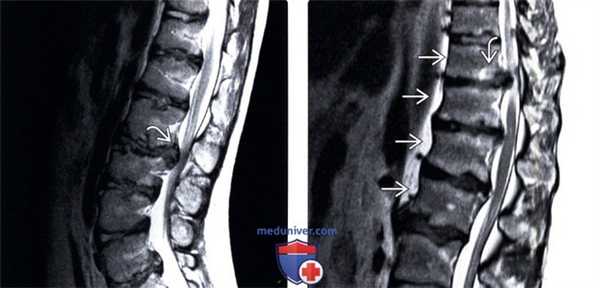

3. МРТ при синдроме Бертолотти:

• Т1-ВИ:

о МР-анатомия, соответствующая переходному каудальному поясничному сегменту

• Т2-ВИ:

о Гиперинтенсивность Т2-сигнала в области неоартроза и прилежащих участках костного мозга, согласно литературным данным, не является характерной особенностью данного состояния

(Слева) Т2-ВИ, аксиальная проекция: признаки переходного пояснично-крестцового сегмента с частичной сакрализацией слева.

(Справа) На представленной фронтальной трехмерной КТ-реконструкции отмечается наличие аномального псевдосочленения тела каудального поясничного позвонка с крестцом и подвздошной костью.